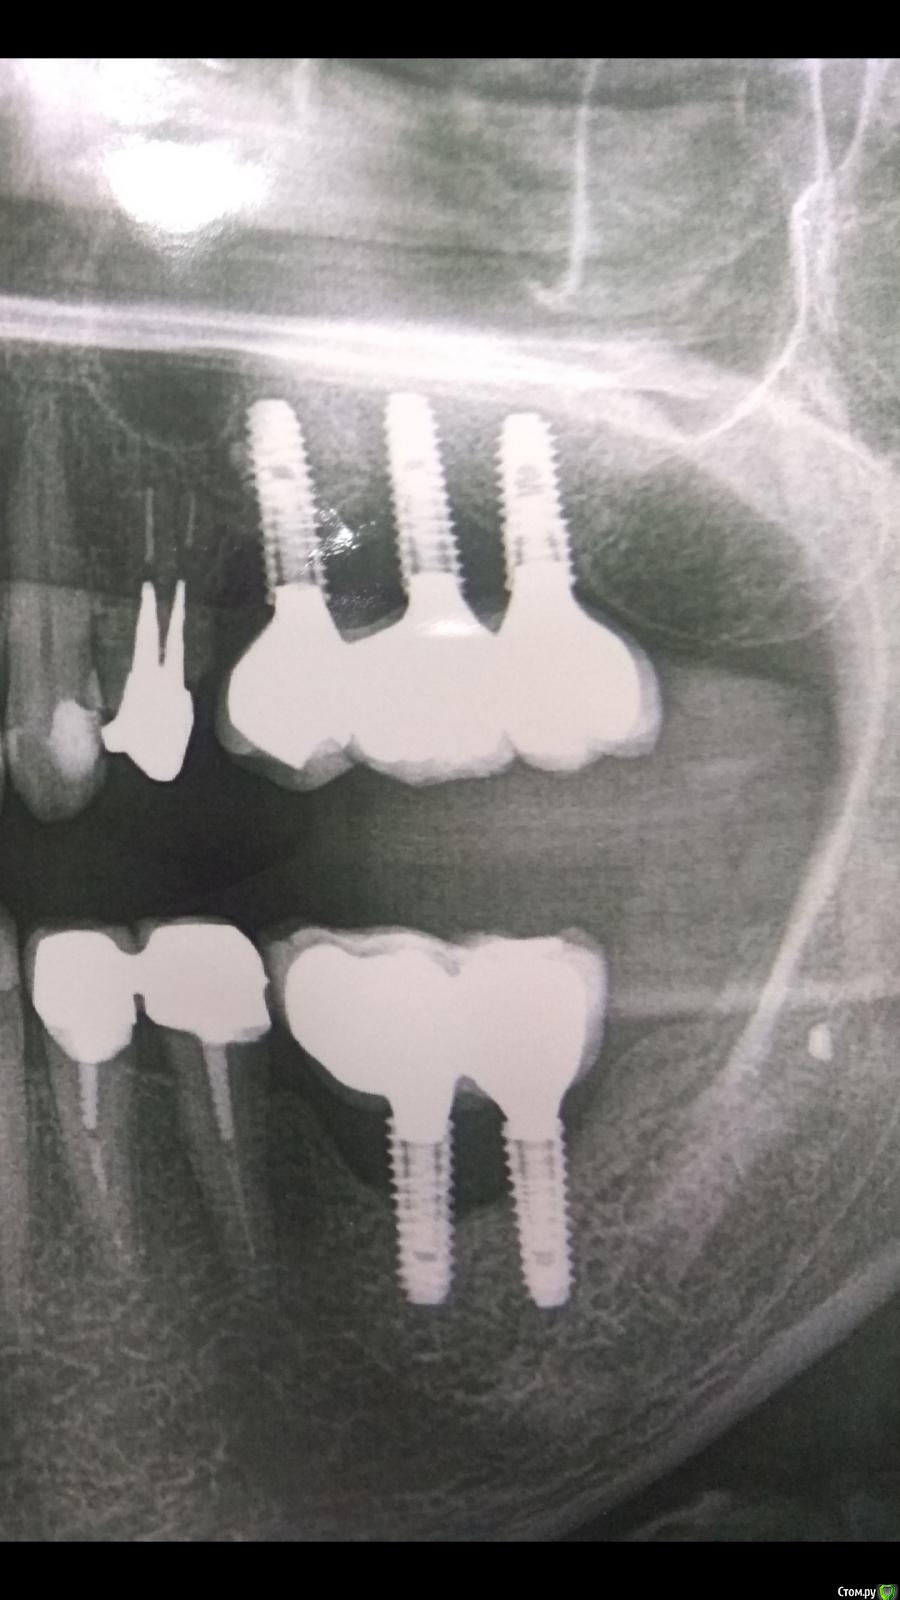

rimtar Опубликовано 16 ноября, 2020 Поделиться Опубликовано 16 ноября, 2020 года 4 , как сдали работу. синус/импланты мои. пациентка жаловалась, что не может жевать левой стороной, зубы не смыкаются. ортопед с техником что-то переделывали, но как оказалось без особого эффекта.недавно обратилась с жалобами на боли слева.орто:снял левую сторону, удалил подвижный 26 имплант.смутили очень короткие конусы, коронки держатся только на винтах:гигиена в порядке. есть проблемы с щитовидной, недавно тотальное удаление.буду благодарен, если укажете на причину , дабы вновь не повторить. Ссылка на комментарий

annda Опубликовано 16 ноября, 2020 Поделиться Опубликовано 16 ноября, 2020 (изменено) Что то мне кажется, что спиливали конусы для видимости пассивной посадки мостов. Оригинальная ли протетика, хотя тут уже это не имеет значения. Если только на винтах, то возможно и микроподвижность была с передачей напряжения на хрупкие шейки имплантатов, размер- то невелик. А оттуда и на кость, которая и ушла благополучно. Это если не видеть окклюзионных взаимоотношений антагонистов имплантат- имплантат , были ли смещающие контакты, ну и все такое. Справа тоже по ним звучит колокол.А что за система? Изменено 16 ноября, 2020 пользователем annda 2 Ссылка на комментарий

rimtar Опубликовано 16 ноября, 2020 Автор Поделиться Опубликовано 16 ноября, 2020 (изменено) про спиливание конусов ортопед сказал, но я не поверил, что такое практикуется. якобы проблемы с параллельностью так решаются.импланты осстем, остальное не оригинал, что именно- не знаю.и первый сегмент уходит, тоже понятно. Изменено 16 ноября, 2020 пользователем rimtar 1 Ссылка на комментарий

kramer Опубликовано 17 ноября, 2020 Поделиться Опубликовано 17 ноября, 2020 1. Выжигаемые абатменты -> негерметичное соединение-> периимпьантит2. Металлокерамика -> отсутствие эпителиального барьера Возможно есть проблемы с пассивностью посадки, хотя это само по себе не приводит к периимплантиту. В спиливании индексов также нет ничего страшного. Эти вещи могут привести к техническим осложнениям, а их не произошло. Мне кажется, основная проблема - негерметичное соединение В общем накосячил ортопед, но свалят на хирурга 1 Ссылка на комментарий

stommm Опубликовано 17 ноября, 2020 Поделиться Опубликовано 17 ноября, 2020 Имхо главная но не единственная причина. Нахрена глазурь под десной? Так или иначе будет карман. С мультиюнитами было бы намного безопаснее. Под десной должен быть титан или циркон. Но не керамика и кхс 2 Ссылка на комментарий

chervoncevdaniil Опубликовано 17 ноября, 2020 Поделиться Опубликовано 17 ноября, 2020 По идее- то, конечно,непараллельность= мультиюниты и винтовая. Или цементная на индивидуальных. Есть тибэйс без индекса(шестигранника) которые позволяют делать мосты на винтовой фиксации при непараллельности опор,это вообще не проблема,не обязательно через МЮ,у абсолютного большинства нормальных систем имплантов такие имеются Спиливать конусы-это совсем колхоз и изначально бы ни один вменяемый ортопед на это не пошел,так могли сделать только в том случае,если работа не села,а переснимать слепок и переделывать было лень Тут ведь винтовая фиксация,я правильно понимаю? Ссылка на комментарий

chervoncevdaniil Опубликовано 17 ноября, 2020 Поделиться Опубликовано 17 ноября, 2020 Я конечно дико извиняюсь,но никак в толк не возьму одну деталь.Зачем ставить вообще эти абатменты без индекса? То есть не использовать место шестигранника в шахте,а использовать этот маленький цилиндр где коронка держется за счёт винта,не вижу смысла имхо.Лучше мультиюнит,или цементная на индивидуальных абатментахЕсли конусная система и абатмент без шестигранника родной(non engage) то там никаких проблем нет,нагрузка нормально распределяется.По другому мост просто не посадить на винтовой фиксации.То,что сделано здесь,мне не очень понятно,такое чувство что где то было накосячено и сначала взяли абатменты с шестигранникам,а потом поняли что то идет не так и выкручивались как могли. Ссылка на комментарий